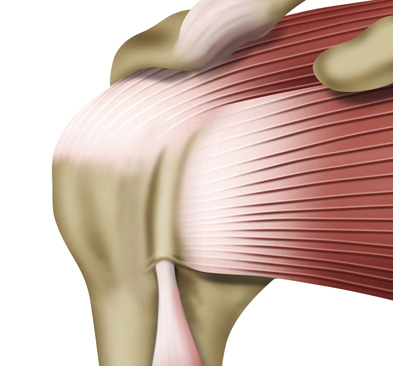

어깨 안에는 어깨 관절을 감싸고 있는 4개의 힘줄이 있습니다.

이 힘줄이 회전근개이며, 회전근개는 관절이 가능한 움직임 내에서 안정성을 유지하는 역할을 하고 있습니다.

이런 회전근개가 하나 또는 그 이상 파열되는 것을 회전근개 파열이라고 합니다.